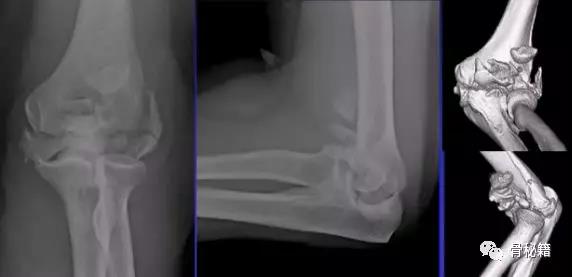

详细的术前评估

X线、CT、神经、等等